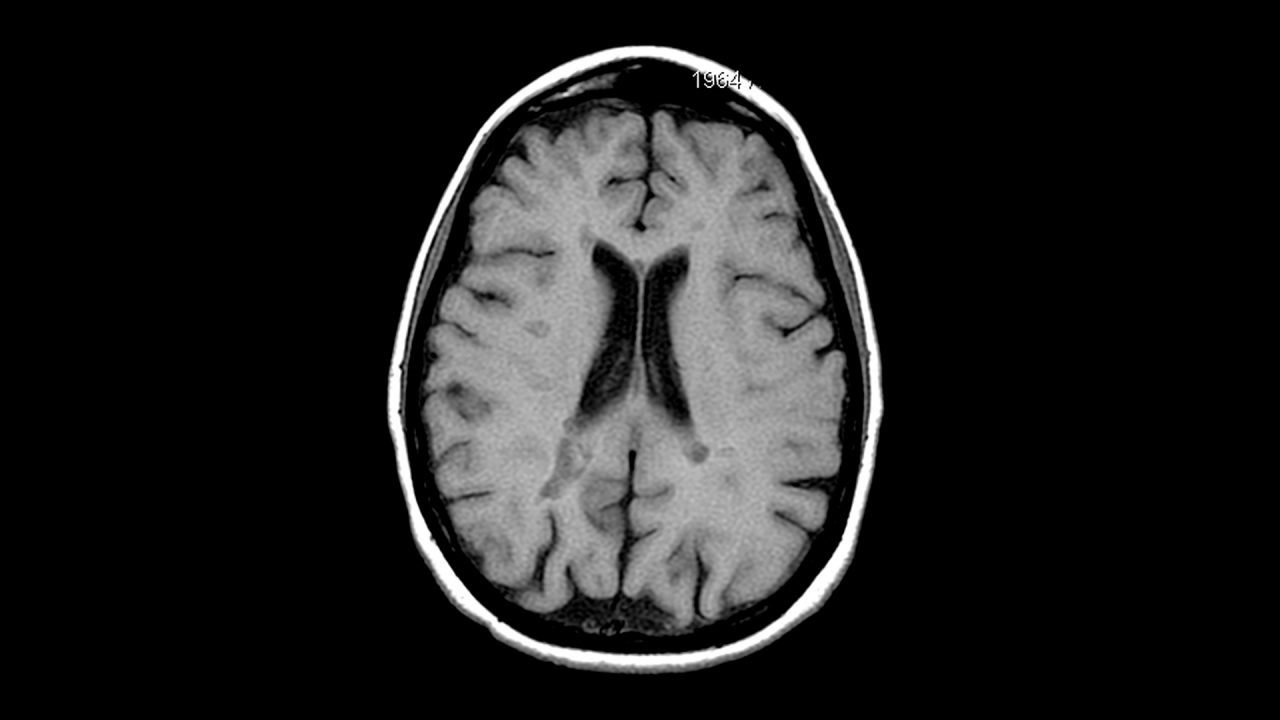

Yapay zekâ alanında yaşanan gelişmeler, sağlık sektöründe de köklü değişiklere kapı aralamaya devam ediyor. Michigan Üniversitesi’nde geliştirilen Prima adlı yeni yapay zekâ modeli, MR sonuçlarının neredeyse anında analiz edildiği bir geleceğin önünü açabilir. Zira Prima, bir beyin MR’ını saniyeler içinde analiz edip tanı koyabiliyor. Üstelik doğruluk oranı da son derece etkileyici. Araştırmaya göre Prima, 50’den fazla tanı kategorisinde yüzde 97,5’e varan doğruluk oranına ulaşabiliyor.

Yapay zekâ alanında yaşanan gelişmeler, sağlık sektöründe de köklü değişiklere kapı aralamaya devam ediyor. Michigan Üniversitesi’nde geliştirilen Prima adlı yeni yapay zekâ modeli, MR sonuçlarının neredeyse anında analiz edildiği bir geleceğin önünü açabilir. Zira Prima, bir beyin MR’ını saniyeler içinde analiz edip tanı koyabiliyor. Üstelik doğruluk oranı da son derece etkileyici. Araştırmaya göre Prima, 50’den fazla tanı kategorisinde yüzde 97,5’e varan doğruluk oranına ulaşabiliyor. Prima, 220 Binden Fazla MR Kullanılarak Eğitildi

Prima, radyolojinin dijitalleşmeye başladığı dönemden bu yana biriken 220 binden fazla MR ve 5,6 milyon görüntü sekansı üzerinde eğitildi. Bu veri ölçeği, sistemi yalnızca belirli görevler için optimize edilmiş dar kapsamlı yapay zekâlardan ayırıyor.

Prima, bir “görsel-dil modeli” (vision language model) olarak çalışıyor. Yani yalnızca görüntüleri değil, aynı anda metin verilerini de işleyebiliyor. Hastanın tıbbi geçmişi, doktorun görüntüleme talep nedeni ve MR’daki tüm sekanslar birlikte değerlendirilerek bütüncül bir analiz yapılıyor.

Bu alanda daha önce test edilen yapay zekâlar genellikle belirli bir hastalığa odaklanan ve manuel olarak seçilmiş veri setleriyle eğitilen sistemlerdi. Prima ise farklı lezyon türlerini kapsayan 52 radyolojik tanıda performans gösterebiliyor. Yaklaşık 30 bin MR görüntüsü üzerinde bir yıl boyunca yapılan testlerde sistem, hastalık olan vakalarla sağlıklı olanları ayırt etmede ortalama yüzde 92 başarı oranına ulaştı ve bu alandaki mevcut gelişmiş yapay zekâ modellerinden çok daha iyi performans gösterdi.

Prima’nın dikkat çeken yönlerinden biri de yalnızca tanı koymakla kalmayıp iş akışını optimize edebilmesi. Örneğin beyin kanaması ya da inme gibi acil müdahale gerektiren durumlarda ilgili sağlık ekiplerini otomatik olarak uyarabiliyor ve hangi alt uzmanlık alanındaki hekimin bilgilendirilmesi gerektiğini belirleyebiliyor. Bu da özellikle zamanın hayati önem taşıdığı vakalarda sonuçların daha hızlı alınmasına katkı sağlayabilir.

Araştırmacılar, doğruluğun beyin MR’ı yorumlamada temel kriter olduğunu vurgularken, hızlı geri dönüş sürelerinin de hasta sonuçlarını doğrudan etkilediğine dikkat çekiyor. Dünya genelinde her yıl milyonlarca MR çekimi yapıldığı için oluşan iş yükü radyoloji hizmetlerinin kapasitesini aşmış durumda. Bazı sağlık merkezlerinde sonuçların çıkması günler, hatta haftalar sürebiliyor. Prime ve benzeri yapay zekâların ortaya çıkması, bu noktada radyaloji uzmanlarının işini fazlasıyla kolaylaştırabilir

Prima’nın geliştirici ekibi, ilerleyen aşamada elektronik sağlık kayıtlarının da modele entegre edilmesini planlıyor. Böylece klinik bağlamın daha güçlü şekilde analize dâhil edilmesi ve tanısal doğruluğun daha da artırılması hedefleniyor.